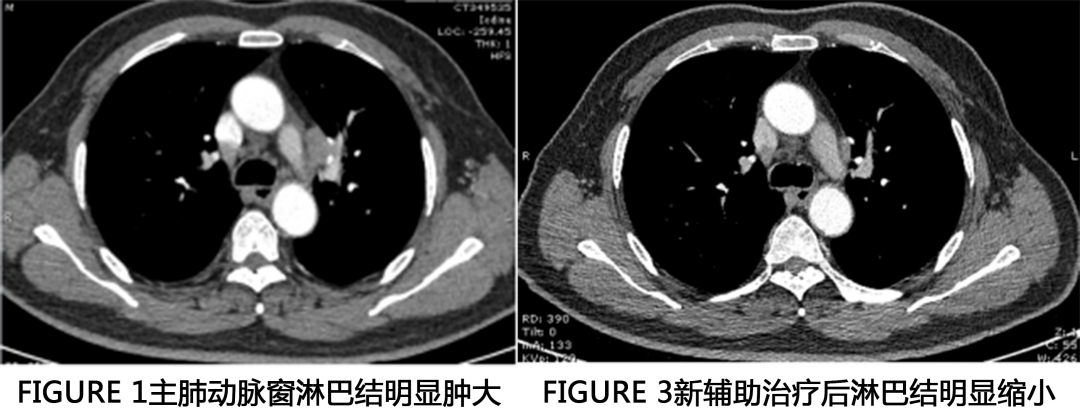

患者陈先生68岁。2月前因右侧肋部外伤到当地医院就诊,拍了胸部CT显示左舌段占位伴阻塞性改变,纵隔及左侧腋窝淋巴结肿大,肺癌可能性大。

患者在多方医生的帮助下,为进一步缩小肿瘤、降期及增加手术机会,做了新辅助化疗与靶向治疗。化疗方案为:培美曲塞二钠1.0 D1+卡铂 0.6 D1;基因检测:EGFR21外显子突变、Hert2突变,2021-01-11加用阿美替尼治疗。

患者在多方了解下,近期来我科室找到了邵丰主任,复查了CT。

邵主任在多方判断下,病人可以手术切除病灶,术前分期检查也未见明显远处转移。手术方式为全麻单孔胸腔镜下行左上肺叶切除+淋巴结清扫术。

患者进行新辅助化疗后手术难度明显增大,尤其是病灶退缩部位,硬的像钢板,毫无间隙和层次可言,需要医生的耐心和胆量。邵主任从医多年,手术很顺利,历时1.5小时,术中出血仅50ml。

术中见主肺动脉窗淋巴结及肺门淋巴结冻结明显,肺门结构纤维化明显,分离困难,完美避开喉返神经,术后患者也无明显声音嘶哑症状。